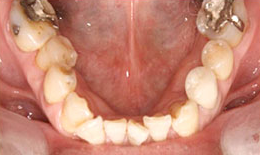

インプラント症例(5) 58歳 男性

治療前